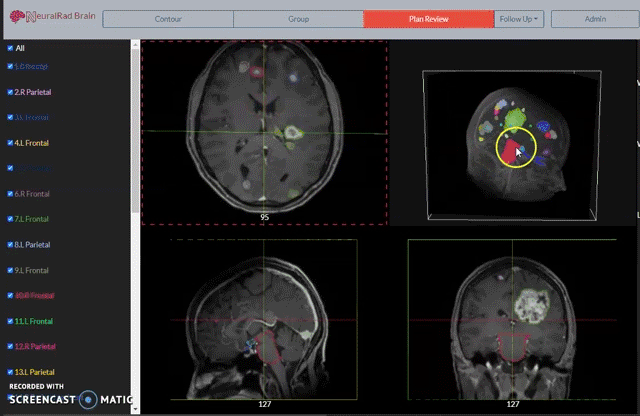

在众人的帮助和努力下,历经多年,终于在不久前开发出了以下三种 AI 模型:

自动勾画/标记脑转移瘤病灶的模型;

基于 SVM-放射组学,能快速减少假阳性的模型;

基于优化辐射剂量图,能快速分割多个病灶到不同治疗疗程的模型。

三种模型相辅相成,对应到医生的工作流程中,能大幅减少使用立体定向放疗时的工作量。